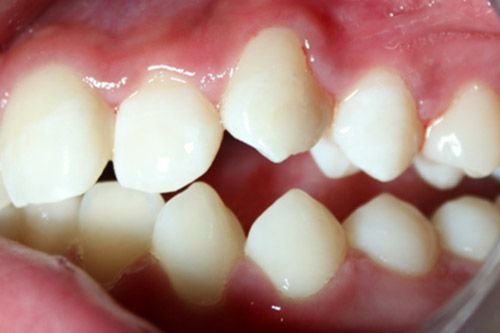

Opacidades bien delimitadas en incisivos o molares en el tercio oclusal y/o incisal que afecta a una o dos superficies, sin involucrar las cúspides y sin fractura del esmalte al erupcionar aunque puede ocurrir post-eruptivamente debido a la función. Presencia de restauraciones atípicas intactas. Hay compromiso estético y la sensibilidad es normal.

Grado 3: Severa

Pérdida post-eruptiva del esmalte y fracturas. Presencia de caries extensas asociadas al esmalte defectuoso y/o presencia de restauraciones típicas defectuosas, con compromiso de la estética e hipersensibilidad.